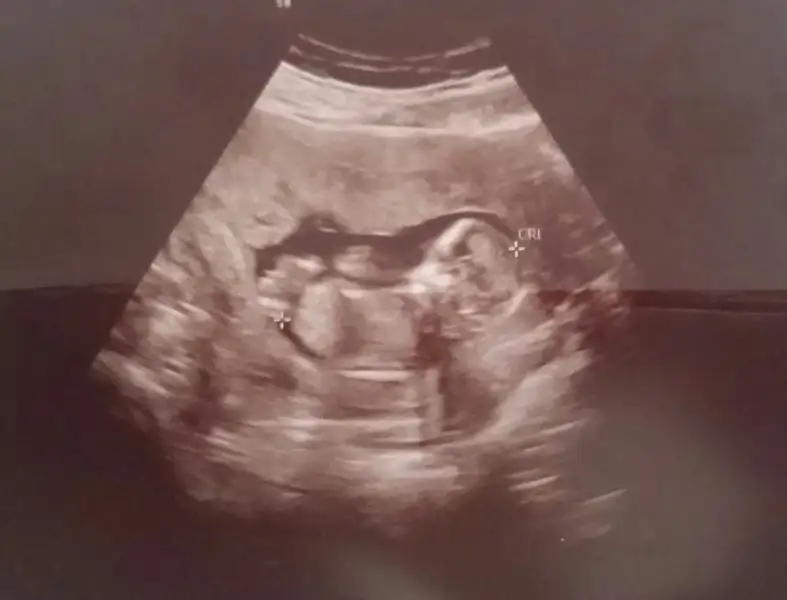

Kızlar resimden anlaşılıyor mu bişey net değil galiba cinsiyet için 13 haftalık

Bu nub bacak arası mı oluyor? Yukarı doğru kalkık olanlar bacak değil mi? Benim ufaklık içinde bir tahmin yapar mısınız? Eki Görüntüle 2091858 Eki Görüntüle 2091858

Ne kadar net çekilmiş bir üsg ilk defa bu kadar net görüyorum , tam bir erkek hem de bacaklarını açmış biri saga biri sola sağa taraf olan biraz belli olmuyor soldaki tam belli bir de kıvrık olan da kordon bağı :) maşallah canım Rabbim nazarlardan korusun sağ salim doğsun inşallah